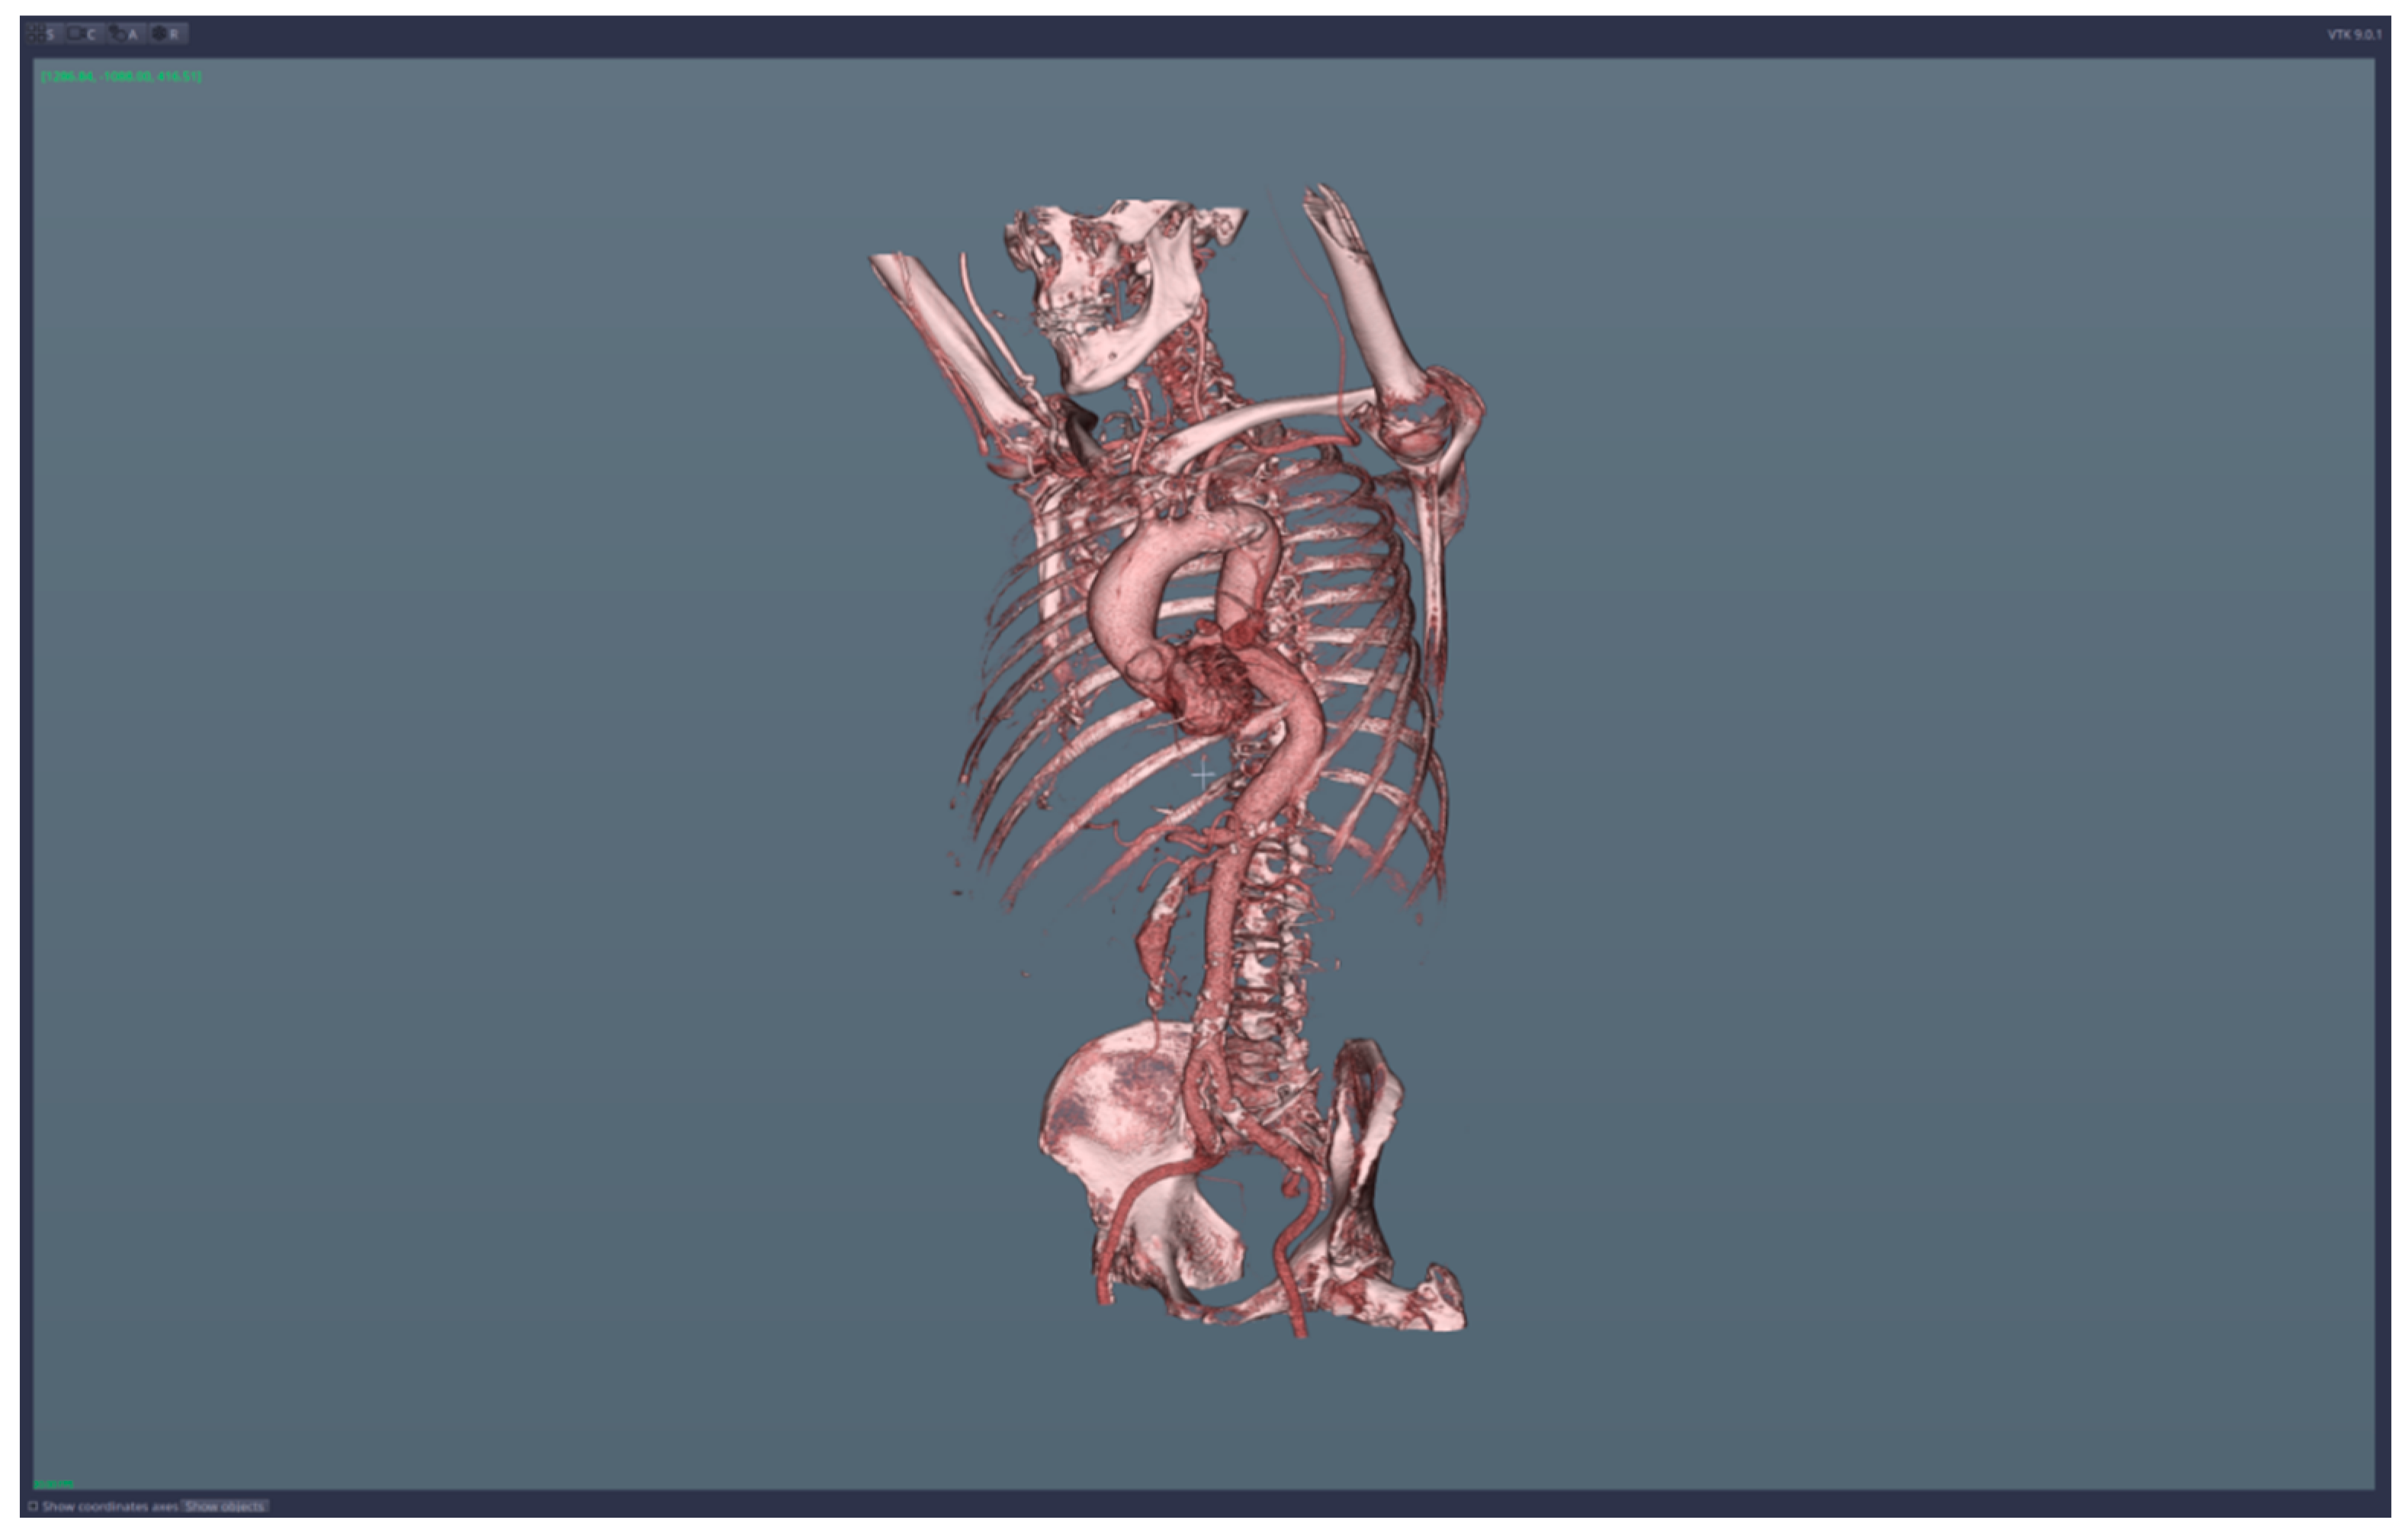

• 3D reconstruction and visualization of arteries (see Figure 1 and Figure 2)

The 3D reconstruction and the visualization of arteries are based on the concept of a transfer function, which translates Hounsfield units from the CT data into colors and levels of opacity for the 3D-rendering scene. CardioCTNav implements a “freehand” drawing mode of the transfer function shapes; in this way, it allows fine-tuning in the selection of the tissues that are visualized (this fine-tuning is necessary for virtual navigation/angiography).

We applied the suggested pre-operatory planning procedure on CT data from a male patient aged 74. The scans were performed using a Siemens Somatom go. Top 128 slice machine [18], with contrast substance (ULTRAVIST 370 I.V.). The series used for planning took 647 slices at a distance of 0.99 mm each. The reconstructed 3D image had 655 × 512 × 647 voxels.

Figure 1. Images of the 3D CT reconstruction and 2D sections.

Figure 2. Images of the 3D reconstruction of main arteries and mesenteric artery aneurysm.